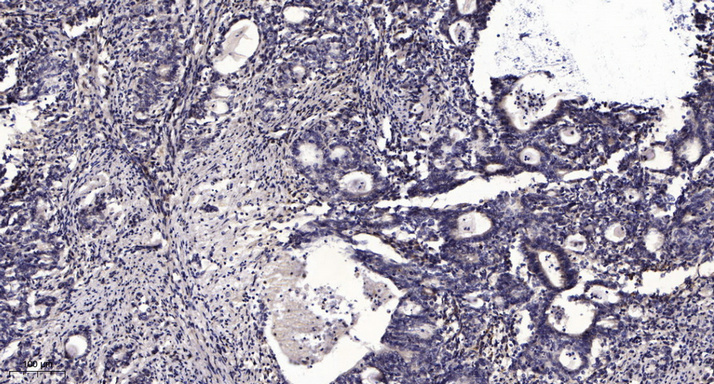

WB, IHC, IF, IP

Optimal working dilutions should be determined experimentally by the investigator; Suggested starting dilutions are as follows:IHC 1:50-300; IF 1:200.

α-tubulin Monoclonal Antibody(8F11) AbFluor™ 680 Conjugated specially designed for your Immunofluorescence analysis.

α-tubulin Monoclonal Antibody(8F11) AbFluor™ 680 Conjugated specially designed for your Immunofluorescence analysis.